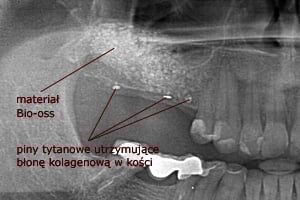

W metodzie z wypreparowaniem okna bocznego jesteśmy w stanie uzyskać nawet do 10mm nowej, świeżo utkanej tkanki kostnej, jednak przed wprowadzeniem implantu, wymagane jest odczekanie około 6-9 miesięcy w celu uzyskania przebudowanej, uformowanej nowej kości zdolnej do przyjęcia wszczepu. Niekiedy istnieje możliwość jednoczasowej implantacji wraz z zabiegiem podniesienia dna zatoki przy korzystnych relacjach ilości własnej kości do kości nowo tworzonej po zabiegu podniesienia dna zatoki. Postępowanie takie pozwala przyspieszyć zakończenie leczenia o okres późniejszego oczekiwania na osteointegrację implantu.

W każdej z metod, po odwarstwieniu błony Schneidera (błony śluzowej wyścielającej ściany zatoki), w wytworzoną przestrzeń wprowadzany jest materiał kościozastępczy będący zrębem dla powstawania nowej tkanki kostnej.